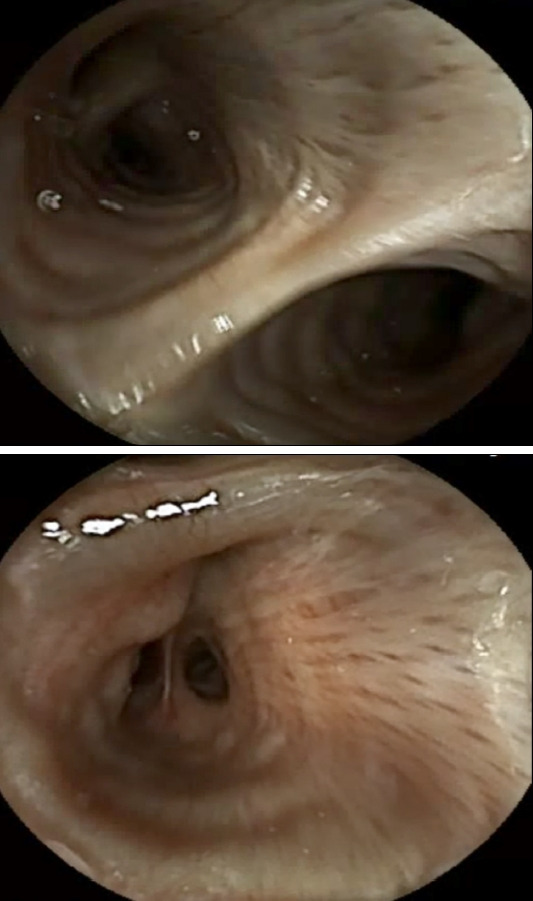

Bifurcated Lumen Observed on Capsule Endoscopy.

胶囊内窥镜观察到分岔管腔